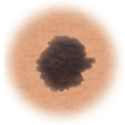

Lunares (nevos)

Son marcas pequeñas en la piel que se deben a las células que producen el pigmento. Los lunares pueden ser planos o elevados, lisos o ásperos y algunos tienen pelos. La mayoría es de color marrón oscuro o negro, pero algunos son amarillentos o del color de la piel. Los lunares pueden cambiar con el tiempo y a menudo reaccionan a los cambios hormonales.

En la mayoría de los casos, los lunares son benignos y no se necesita tratamiento. Algunos lunares benignos pueden convertirse en cáncer de piel (melanoma). A continuación puede consultar los signos de que un lunar se está volviendo canceroso.

Cómo distinguir los lunares benignos de un melanoma

Hay determinados lunares que presentan un mayor riesgo de convertirse en un melanoma maligno, una forma de cáncer de piel. Los lunares que están de nacimiento y los lunares atípicos tienen mayor probabilidad de volverse cancerosos. Es importante detectar las masas de piel cancerosas a tiempo por que así el tratamiento puede ser más eficaz. El tratamiento que mejor suele funcionar consiste en extirpar el melanoma en una cirugía. Si el melanoma se diagnostica a tiempo, suele extirparse todo el cáncer en la cirugía.

Lunar normal.